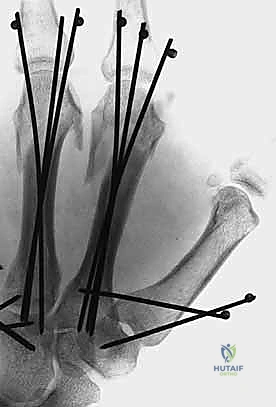

1. التثبيت باستخدام الأسلاك الدقيقة (K-wires)

تُعد هذه الطريقة (Percutaneous Pinning) من التقنيات طفيفة التوغل. يتم إدخال أسلاك معدنية رفيعة جداً عبر الجلد لتثبيت العظم المكسور تحت توجيه الأشعة السينية المستمرة (C-arm) داخل غرفة العمليات.

* الميزة: جروح صغيرة جداً، تعافٍ أسرع للأنسجة الرخوة.

* الإزالة: غالباً ما يتم إزالتها في العيادة بعد 4-6 أسابيع بدون الحاجة لتخدير كامل.

خطوات التثبيت الجراحي - توثيق بصري (Intraoperative Imaging)

يحرص الدكتور هطيف على توثيق خطوات العمل الجراحي لضمان أعلى مستويات الدقة. نستعرض هنا مجموعة من الصور من داخل غرفة العمليات توضح مدى تعقيد ودقة هذه الجراحات:

تتطلب الجراحة انتباهاً خاصاً للأوتار الباسطة والقابضة والأعصاب الدقيقة المحيطة بالعظام. استخدام تقنيات الجراحة الميكروسكوبية (Microsurgery) يضمن عدم الإضرار بهذه الأنسجة الحساسة.